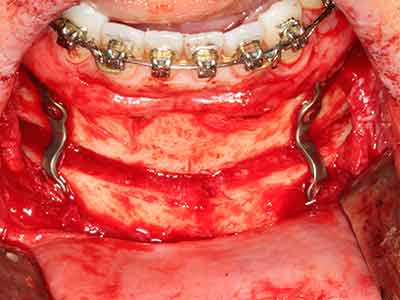

En la extracción de bloques óseos la piezocirugía también presenta ventajas adicionales: Además de la alta precisión en la osteotomía que ya se ha descrito antes, se ha comprobado que el uso de los delgados insertos de sierra resulta especialmente cuidadosas con el hueso. Frente a esto, sobre todo cuando se usan las fresas de Lindemann, cabe esperar pérdidas en la extracción significativamente más altas debido al mayor grosor de la parte frontal del cabezal (Lakshmiganthan, Gokulanathan et al. 2012). La separación basal que se necesita en particular en los injertos de bloque extraídos de forma retromolar se ve facilitada mediante sierras perpendiculares especialmente previstas a tal fin, lo que permite considerar que la cirugía piezoeléctrica es un procedimiento preciso y seguro para la obtención de bloques de hueso en el área retromolar (Happe 2007) (fig. 1-12).

El tejido óseo no solo tiene un contenido puramente mineral, sino que también presenta una importante proporción de fibras de colágeno. Esto no solo garantiza una buena resistencia a la presión, sino también una cierta flexibilidad, que puede aprovecharse para la realización de aumentos. En la plastia de expansión clásica a efectos de una partición ósea, la cresta maxilar atrofiada se divide en su eje longitudinal y, tras alcanzar una profundidad de osteotomía suficiente, se extiende con cuidado (fig. 13-16), en un caso ideal sin desperiostizar de forma visible el maxilar (Brugnami, Caiazzo et al. 2014, Stricker, Fleiner et al. 2014). Los sistemas de tornillos y placas con distancia de expansión creciente han demostrado su eficacia para distanciar entre sí las dos tablas óseas por debajo del umbral de rotura. Por regla general, se requieren anchuras de hueso residual de al menos 3 a 4 mm (Chiapasco, Zaniboni et al. 2006) para garantizar una flexibilidad y una cobertura ósea suficientes de los implantes que van a incorporarse. En caso necesario, una osteotomía de descarga vertical unilateral o bilateral puede mejorar la flexibilidad. Como alternativa a la técnica clásica se ha descrito una combinación con otras técnicas de aumento, sobre todo en la parte bucal.

Con el uso de sierras piezoeléctricas la división se efectúa de forma especialmente cuidadosa y sin pérdidas importantes de las dimensiones, por lo que no se han encontrado diferencias significativas entre los implantes realizados en el maxilar dividido y en la cresta alveolar no deficitaria (Chiapasco, Zaniboni et al. 2006, Danza, Guidi et al. 2009). No obstante, precisamente en la partición profunda y limitada de forma local, es preciso asegurarse de que exista una adecuada irrigación por agua para evitar que se produzcan sobrecargas térmicas en las áreas de osteotomía apical.